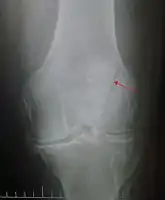

A vertical patella fracture with the fracture line marked by a black arrow

Diagnosis is based on symptoms and confirmed with X-rays.[3] In children an MRI may be required.[3]